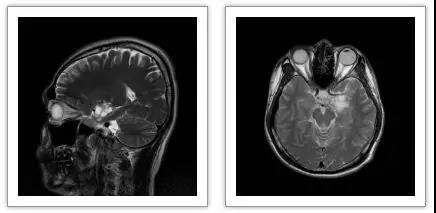

2018年8月,一名21岁体检者经MRI检查拟诊断为“低级别胶质瘤”。

【低级别胶质瘤,指低度恶性的胶质瘤,临床症状隐匿不易发现,病情发展迅速,早期发现有利于患者的治疗和愈后】

2017年11月,一名47岁体检者经MRI检查拟诊断为“大脑动静脉畸形”。【大脑动静脉畸形,AVM,是一种先天性局部脑血管发生学上的变异。临床症状隐匿不易发现,死亡率高达10%,早期发现有利于患者的治疗和愈后】